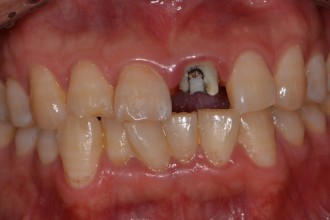

임플란트